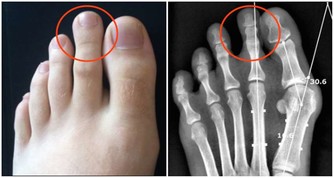

5.扳足趾

△方法:端坐,兩腿伸直,低頭,身體向前彎,用雙手扳足趾20-30次。

△功效:此方法可以強腰腿、增腳力。